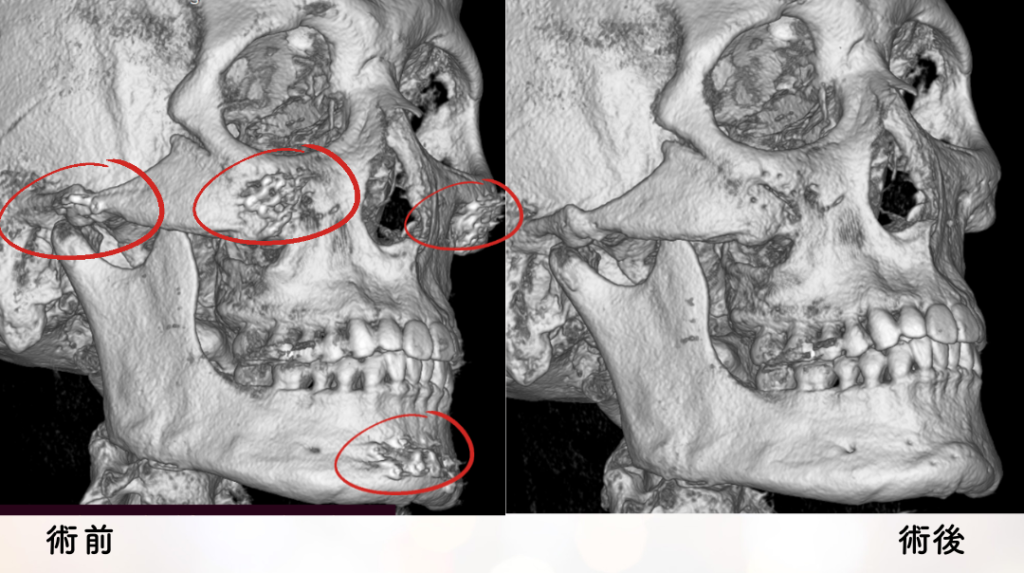

CTでプレートを確認する

頬骨前面に3箇所ずつ、頬骨弓に1個ずつのプレート、オトガイは真ん中に1つ左右に1個ずつの計3個のプレートが留まっています。CT上はオトガイのプレートは埋まっていることが予想されます。。

術後3か月の検診

CT撮影を行い骨の状態も確認しました。すべてのピン・プレートが除去され画像でもスッキリしたのがわかります。やってよかった!と感想をいただけました。

CT術前術後の比較 右斜め

CT術前術後の比較 左斜め